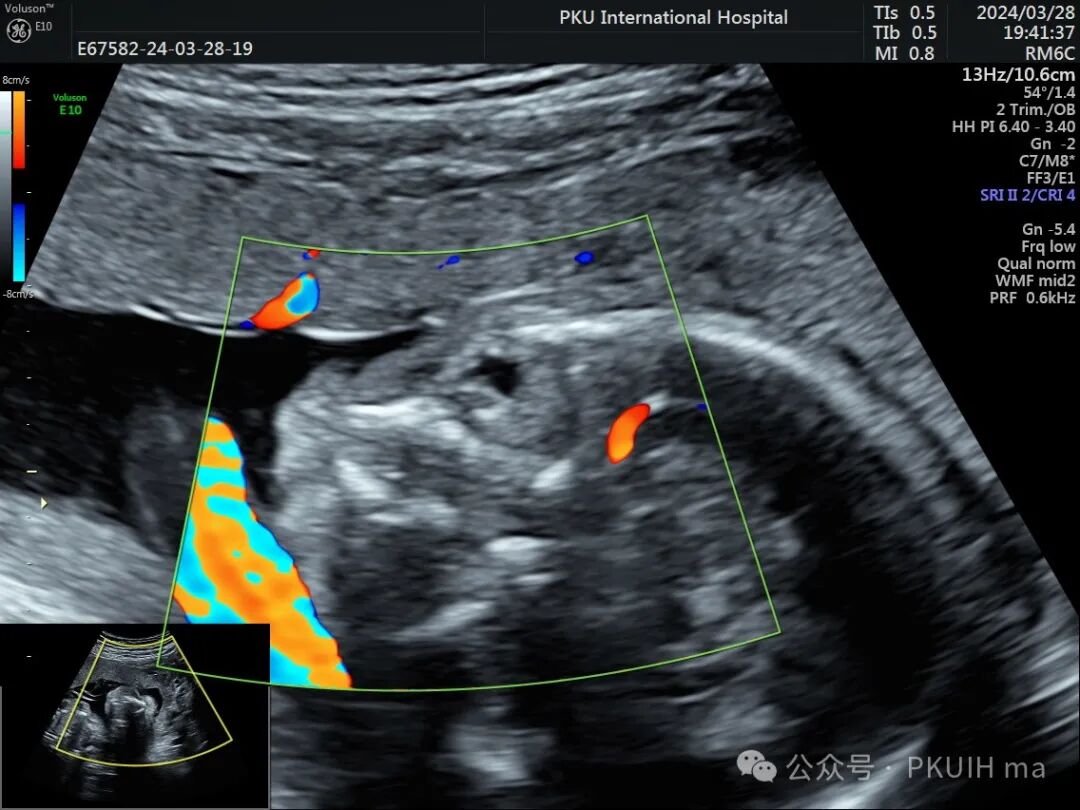

右眼晶状体后方见高回声区,其内未探及血流信号

右眼球情况:两个手标分别代表晶状体和后方的永存玻璃体

实时动态观察双眼发育不对称,右眼小;两侧眼球内晶状体、玻璃体均可见,右侧晶状体小,晶状体后缘玻璃体内见不规则的高回声区。

PHPV的超声表现:一侧眼球晶状体后方可见Y形高回声或强回声条带,或者是晶状体后方圆形或圆弧状高回声团块(直接征象);同时伴有患侧眼球小,晶状体形态异常,眼轴短,部分有玻璃体浑浊。双眼发病极为罕见,表现双层晶状体浑浊,内见不规则强回声或高回声带。CDFI:部分病例可见增生的玻璃体动脉内见血流信号。该病容易反复发生眼内出血,纤维血管性肿块的收缩可能对视网膜产生牵拉,导致视网膜脱离。因此,眼部超声表现可能会随着妊娠进展而改变。